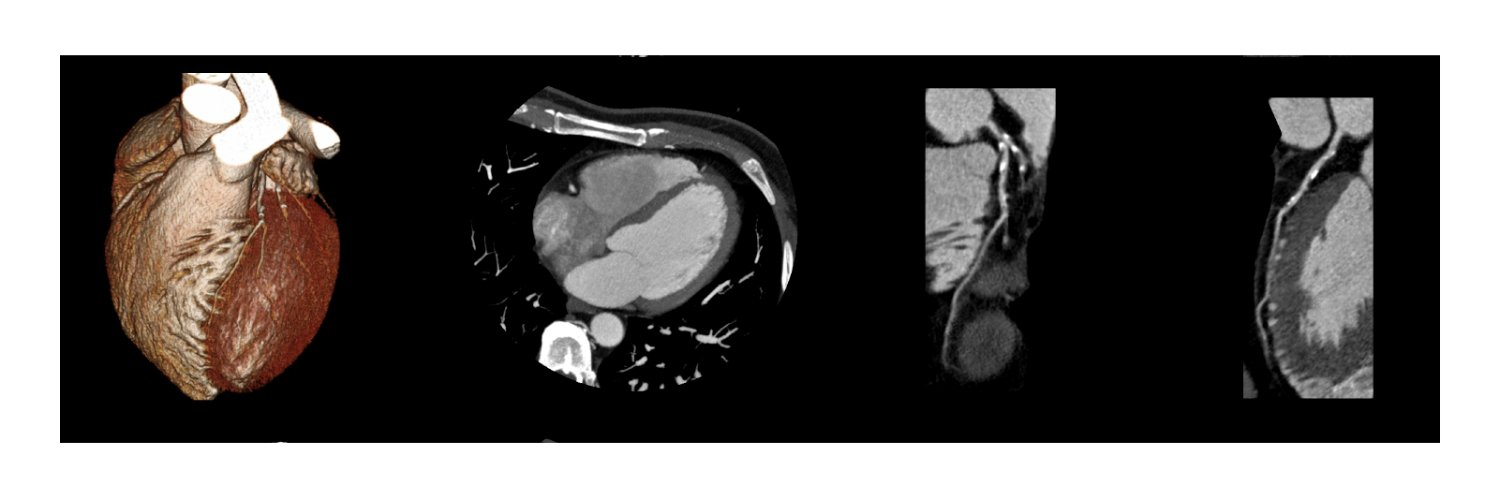

🏆 SCCT Best Original Science Award goes to Dr. Joel Lenell, MD, PhD at the 20th Annual @Heart_SCCT Scientific Meeting! Supported by @CVRF_SoCal and @CVMGBevHills His winning abstract: “Intensive Medical Treatment Reduces Non-calcified Coronary Plaque in Women With Non-obstructive CAD”—powered by AI-enabled plaque analysis in the WARRIOR trial. 📖 Read more: scct.org/news/706265/SC… #CardioTwitter #AIinMedicine #WIC #SCCT2025 #CVImaging #PreventiveCardiology #WARRIORtrial #CAD #HeartHealth @Cardiac_Wire @DanielKarlsberg @BudoffMd @Cleerlyhealth @RayDalio

Regarding the VA AI calcium score study (ai.nejm.org/doi/full/10.10…): Our team at @CVRF_SoCal led one of the first FDA-cleared validation of AI coronary calcium scoring but not from chest CTs (pubmed.ncbi.nlm.nih.gov/37139562/). In 100 non-contrast CACs, AI matched 3 expert readers with R=0.996. Using CAC-DRS calcification system, AI showed 86% agreement; 14% were reclassified—mostly due to underestimating RCA calcium or overestimating RV density for CAC 0–1 which can be clinically relevant to treatment. Overall accuracy of our study: 89%, aligning with the VA study of 84% using chest CT - encouraging for wide-spread adoption. @khurramn1 @CotsCardiology #calciumscore @Heart_SCCT @DrMarthaGulati @EricTopol @RonBlankstein @CVMGBevHills @CAIALOfficial @BudoffMd #artificalintelligence @elonmusk @WHO @BhavikPatelMD @ACCinTouch